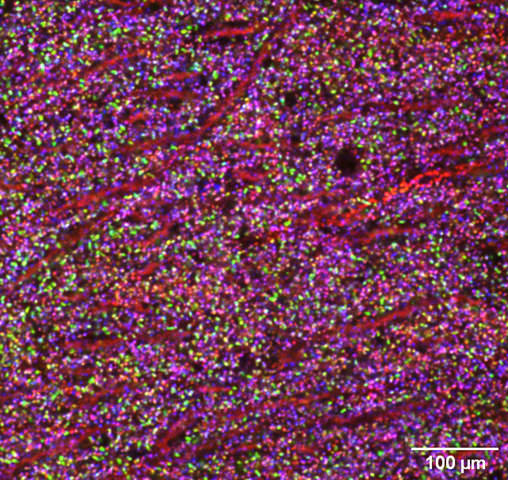

マウスの脳の顕微鏡画像

個々のシナプスを色付きの点として示すマウスの脳組織の画像。3つの異なるタンパク質を緑、赤、青の色素で標識しました。さまざまな色で示されるシナプスの種類の多様性は、これら3つのタンパク質の組み合わせから生じます。